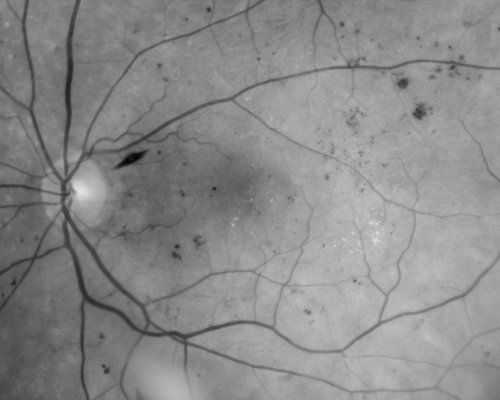

Diabetic Macular Edema Left Eye - Pre Laser

82-year-old woman diabetic for many years, last eye exam 5 years ago with gradual vision loss. OD 20/60, OS 20/70. IOP: OD 16, OS 17.